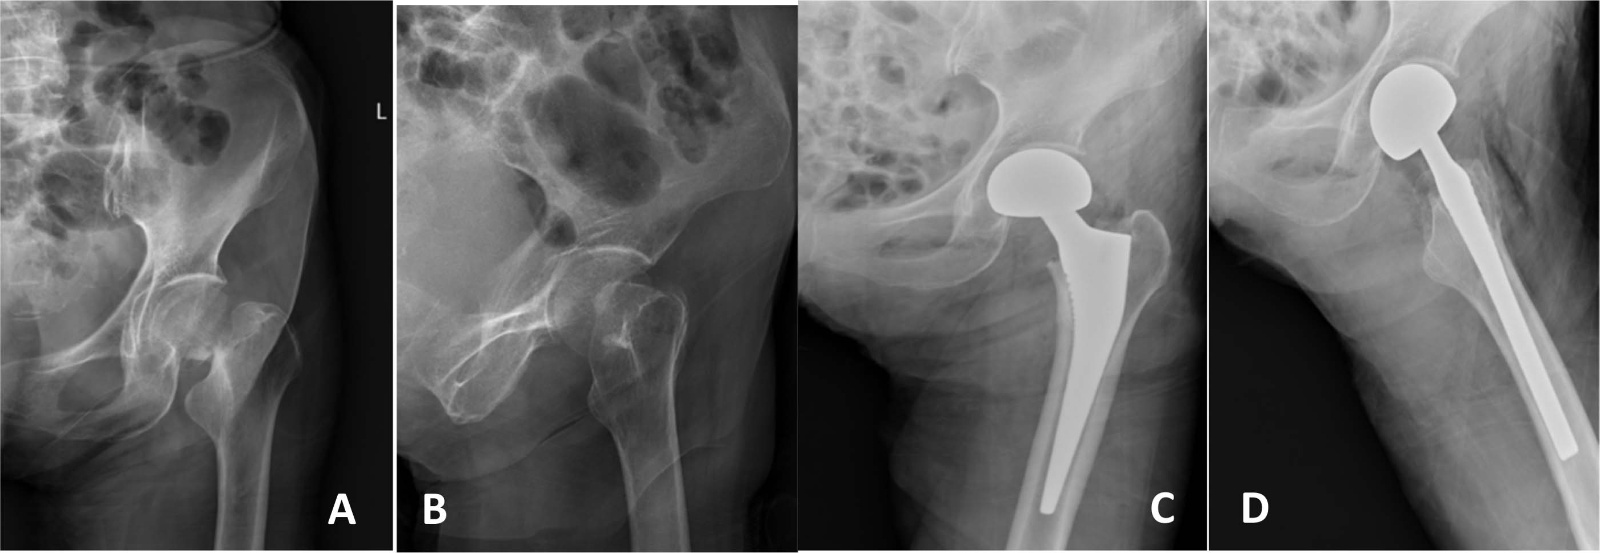

典型病例影像学表现见图1~5图1为76岁女性右侧股骨颈骨折(Garden Ⅲ型)患者,DAA入路半髋关节置换术前X线示骨折断端部分错位,术后X线示假体位置良好,股骨近端微裂予钢丝捆扎固定;图2为83岁女性左侧股骨颈骨折(Garden Ⅳ型)患者,术后X线示假体位置良好;图3为75岁男性右侧股骨颈骨折(Garden Ⅱ型)患者,术后假体位置满意;图4为73岁女性左侧股骨颈骨折(Garden Ⅲ型)患者,术后假体匹配良好;图5为80岁男性右侧股骨颈骨折(Garden Ⅱ型)患者,术后假体位置正常。

Figure 2. X-ray films before and after surgery of an 83-year-old female patient with left femoral neck fracture (Garden type IV) A, B: Before surgery; C, D: After surgery

2. 83岁女性左侧股骨颈骨折(Garden Ⅳ型)患者手术前后X线片A、B:术前;C、D:术后